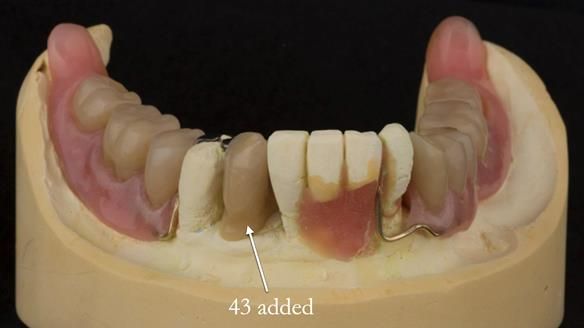

In 2022, tooth 43 fractured.

An artificial tooth was added to the RPD

by welding a cobalt–chrome tag to the bar

and adding the tooth.

The denture continued to function extremely well.